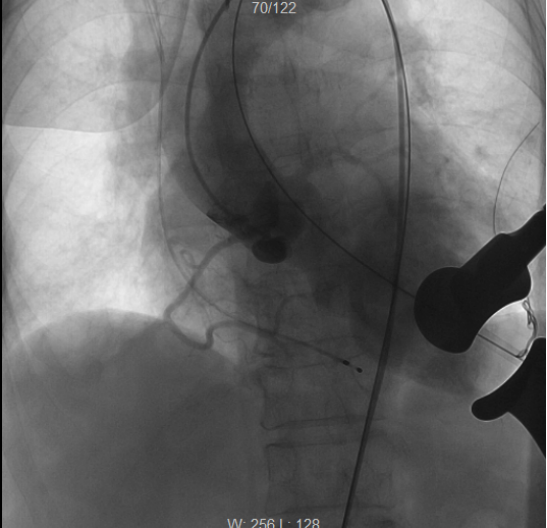

术后再次造影检查,见人工主动脉瓣位置良好,瓣口返流消失